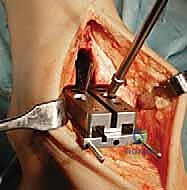

تُجرى العملية عادة تحت التخدير العام أو التخدير النصفي (الشوكي). يقوم د. هطيف بعمل شق جراحي أمامي أو جانبي (حسب التقنية المستخدمة وحالة المريض) للوصول إلى مفصل الكاحل بعناية، مع الحفاظ على الأوتار والأعصاب والأوعية الدموية المحيطة.

3. إزالة الأسطح التالفة (تحضير العظام)

باستخدام أدوات جراحية دقيقة وموجهات خاصة، يتم إزالة الغضاريف التالفة وجزء رقيق جداً من العظام المريضة من نهايتي عظمة الظنبوب وعظمة الكاحل (Talus). يتم تشكيل العظام بدقة لتتطابق تماماً مع شكل أجزاء المفصل الصناعي.

4. تركيب المفصل الصناعي (Implantation)

يتم تثبيت هذه الأجزاء بإحكام (إما عن طريق الضغط المباشر لتشجيع نمو العظم حولها، أو باستخدام أسمنت طبي خاص).

5. إغلاق الجرح والجبيرة